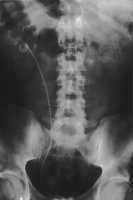

Harnwegsinfekte: Was macht der Urologe und wann sollte er eingeschaltet werden?

Journal für Urologie und Urogynäkologie 2011; 18 (1) (Ausgabe für Schweiz): 32-34 Journal für Urologie und Urogynäkologie 2011; 18 (1) (Ausgabe für Österreich): 31-32 Volltext (PDF) Abbildungen